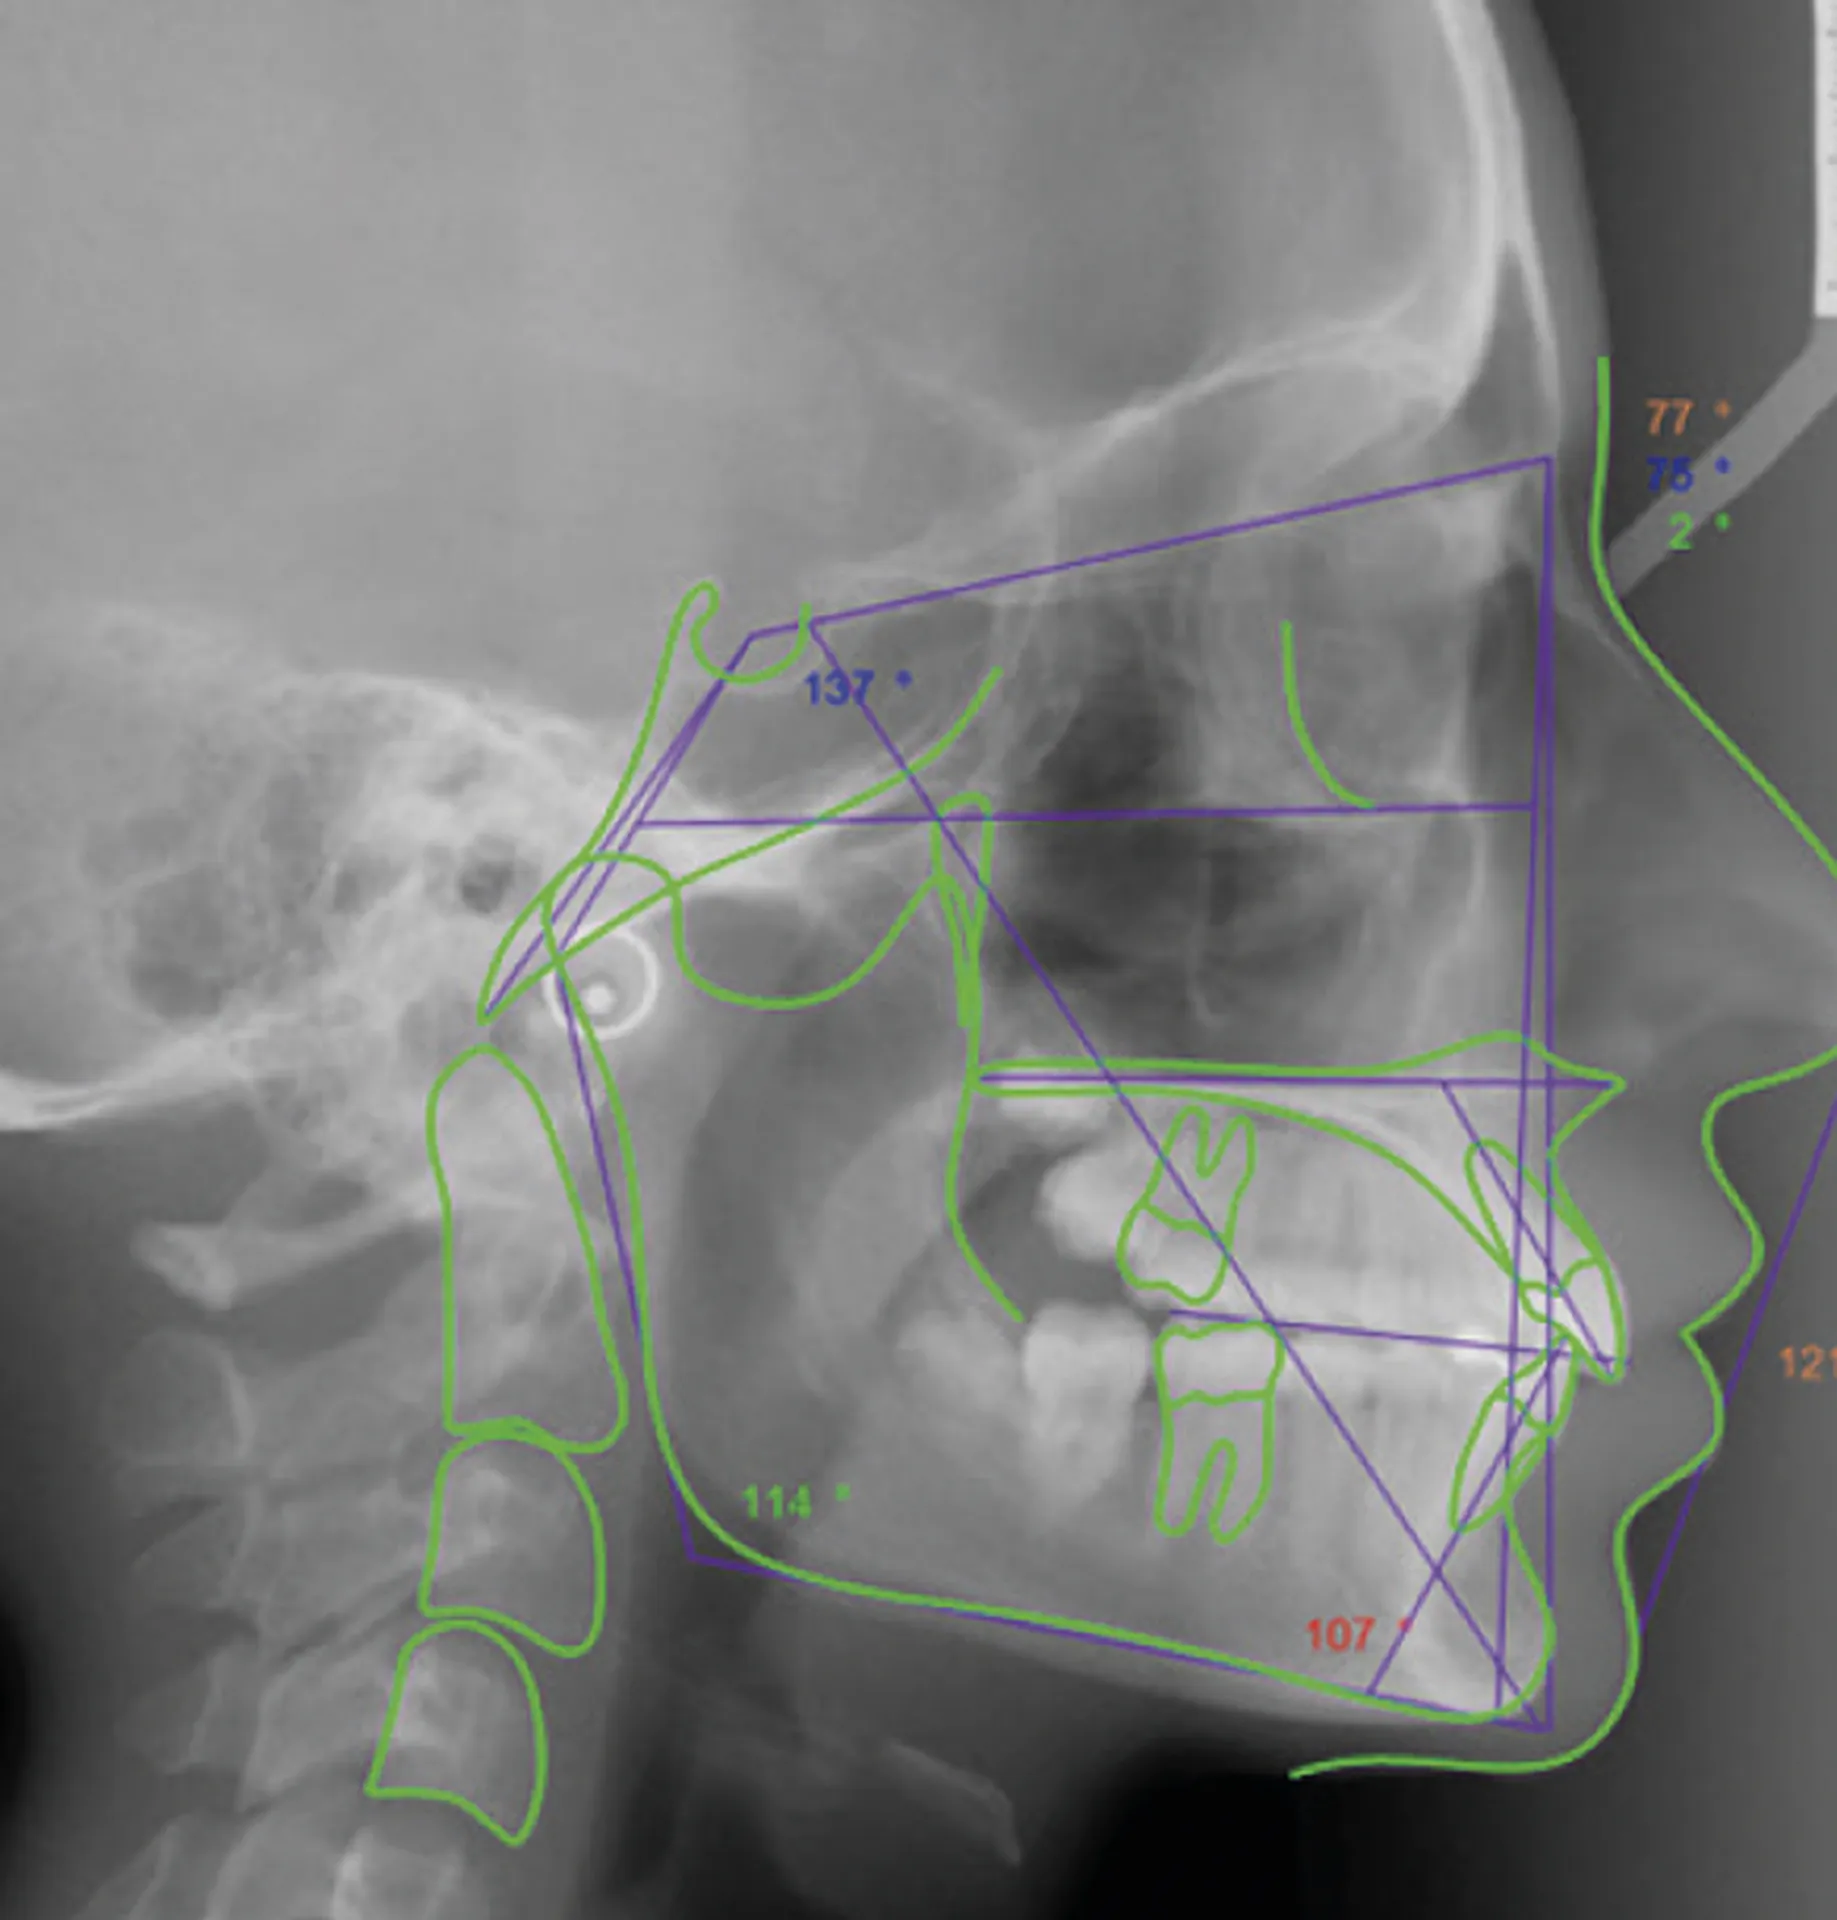

Le logiciel offre une analyse et superposition d’images automatique ou manuelle, permettant de comparer l’évolution du patient et de générer des rapports détaillés. La fonction de projection de croissance simule l’évolution crânienne de l’âge squelettique actuel à un âge futur, offrant une vision prospective du développement du patient jusqu’à la maturité.

Ceph Analysis intègre également des outils de planification de traitement basés sur les prévisions VTO (Visual Treatment Objective) et STO (Surgical Treatment Objective). Ces fonctions permettent de simuler des traitements orthodontiques ou chirurgicaux et d’obtenir des prévisions fiables selon la rigidité des tissus, facilitant ainsi la création de plans de traitement optimisés.

• Plus de 200 types d’analyses céphalométriques intégrées et personnalisables